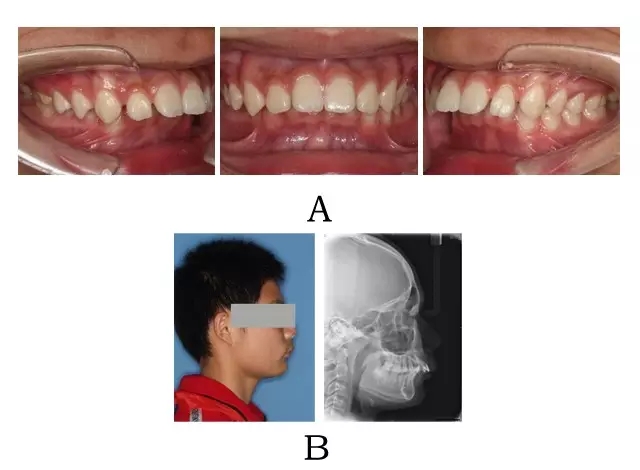

面型前突,面下部高度不足,頦唇溝較深。口內(nèi)表現(xiàn)為上頜骨源性前突,上前牙代償性直立或輕度唇傾;下頜后退伴深覆合深覆蓋,磨牙系遠中關(guān)系。頭顱側(cè)位片下頜骨體部呈“長方形”,頦部形態(tài)較好(圖 4-1)。

圖 4-1:混合 I 型突面畸形臨床表現(xiàn)及頭顱側(cè)位影像特征。

(A)齒槽與牙列特點 (B)側(cè)貌與影像對比

Figure 4-1. Clinical manifestation and cephalometric image for merged skeletal and mandibular positional prognathism (Type I). (A) Alveolar and dentition specifics. (B) Facial profile and radiographic image.